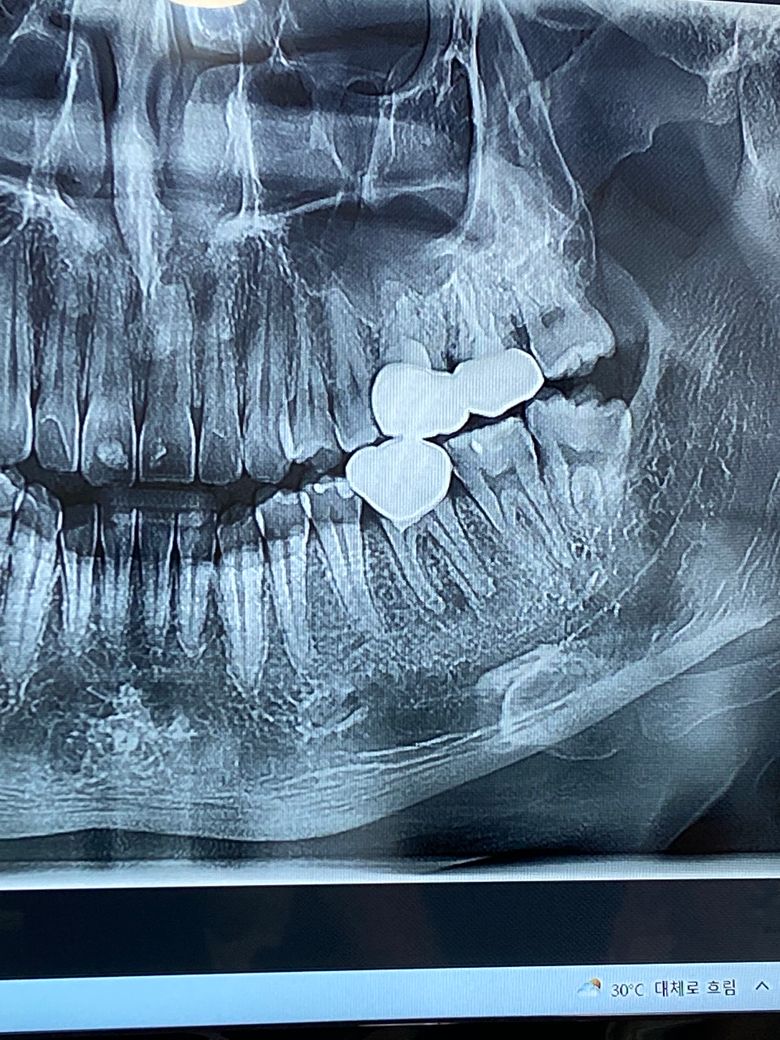

금니 재신경치료, 턱소리 두 가지 질문드립니다.

1. 아래 금니 1개 있는거 재신경치료 해야하는데 통증은없고 저작시 크지않은 통증에

염증이 아마 만성으로 가서 뿌리끝에 염증이있긴하나 큰 증상이 없지만 톡톡 두드리면 살짝불편하고 x레이상 염증이 있기는했다지만 이런경우 빨리 열어야하나요?

ct사진인지 x레이사진인데 사진을 찍어왔는데 보는법을 모르겠어서

보시고 어느정도인지 설명 좀 부탁드립니다 감사합니다!

-사진은 파노라마 사진입니다. 아래쪽 씌우신 치아는 신경치료가 되지 않은 치아 입니다. 불편하시다면 크라운 제거후 신경치료를 하셔야될것같습니다.

1. 사진으로 보았을 때는 재신경치료를 해야할 것으로 보이며 지금은 통증이 없더라도 서서히 나타나거나 해당 염증이 커지면 계속해서 치조골이 소실될 수 있으며 아래에 있는 신경과 근접하면 안면신경 마비도 올 수 있습니다.

사진으로봤을때 염증이 꽤 진행되어있어서 신경치료가 필요한 상황입니다.

현재 통증이 별로 없을지 모르지만, 시간이 지나면서 이가 흔들리거나 통증이 생길 가능성이 높습니다.

하지만 이미 한번 치수절단술을 하였던 치아이기 때문에, 치료를 해도 염증이 없어질 가능성이 높진 않아보입니다.

그래도 염증이 확인된 이상 치료를 하는게 좋아보입니다.